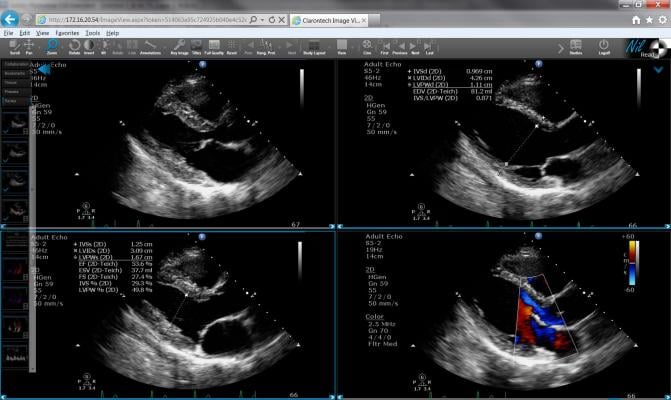

- NilRead Enterprise Viewer, a zero-footprint enterprise diagnostic viewer, gives clinicians universal access to all patient imaging through the EHR or health information exchange (HIE);